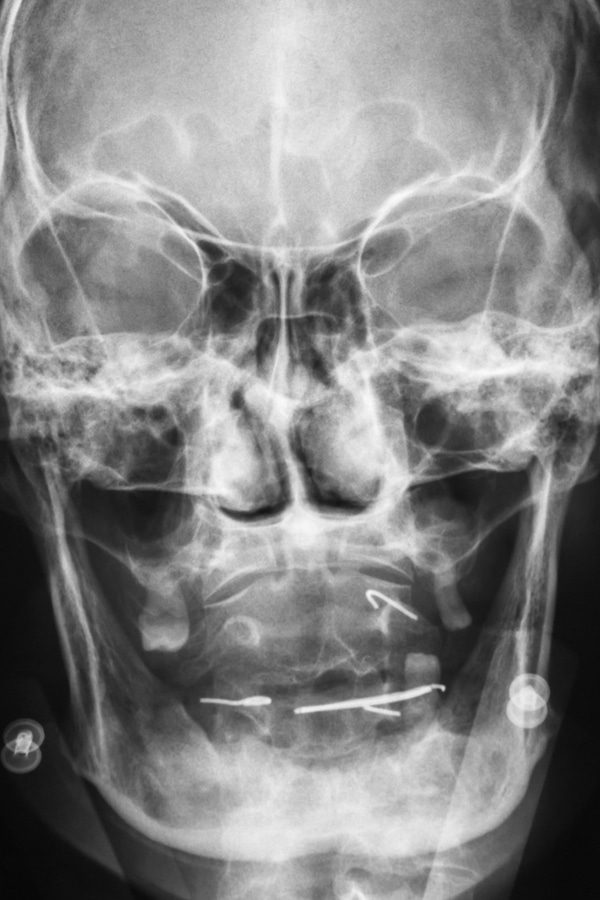

Our doctors have been trained to deliver emergency care for facial trauma involving bones, teeth, and the soft tissues of the face and mouth. However, the first goal of treatment is to stop bleeding, maintain an open airway, repair any fractures, and/or suture damaged soft tissues.